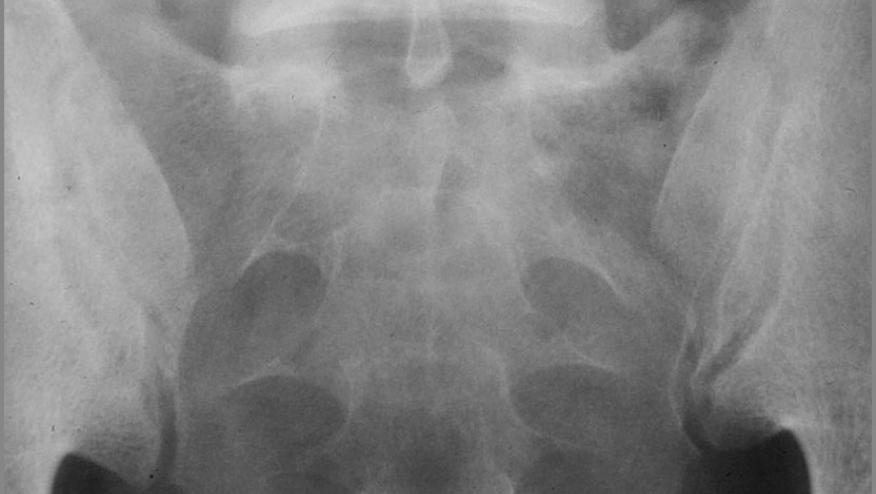

The COAST-X trial was a 1 year placebo-controlled, multinational study of adult patients with active axial spondyloarthritis without definite radiographic sacroiliitis (non-radiographic axial spondyloarthritis-nrAxSpa), manifest with signs of inflammation (MRI or C-reactive protein) but normal radiographs of the SI joint. The primary endpoint was the Assessment of SpondyloArthritis international Society-40 (ASAS40) response at weeks 16 and 52.